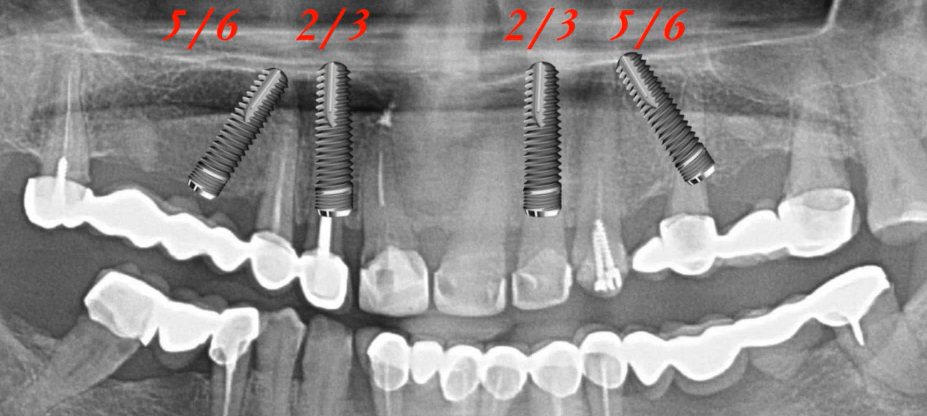

- Rules for implant positioning in the lower jaw. Unless there are special conditions or restrictions, the Full Arch on 4 design typically places implants in the 3 and 6 tooth positions, while maintaining occlusion keys.

However, doctors often encounter bone deficiency in the posterior regions, which shifts the formula slightly and implants are placed in the 2 and 5 tooth positions. This is slightly worse, but it is still possible to create a 12-tooth prosthesis, provided the basic rules are followed:

- The distance between implants is 1.5-2 cm

- The length of the distal cantilevers does not exceed 14 mm

- Guidelines for implant positioning in the upper jaw. It’s best to place six implants in positions 2, 4, and 6.

But if there is a deficiency of bone tissue in the distal sections, which is typical for the upper jaw, then displacement in the positions of teeth 1, 3, 5 is allowed.